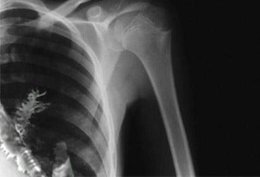

تقریبا مطمئن بودند که آرتیوم مبتلا به نوعی از سرطان در حال رشد است و بهتر است هرچه زودتر تحت عمل جراحی قرار گیرد. در حالیکه آنچه که در حال رشد بوده یک جوانه درخت صنوبر بوده است.طول شاخه صنوبر حدود ۵ سانتی متر بود. احتمالا دانه آن در اثر تنفس داخل ریه آرتیوم شده و بدن آرتیوم نتوانسته آن را دفع یا جذب کند و صنوبر با استفاده از محیط گرم و مرطوب ریه آرتیوم رشد